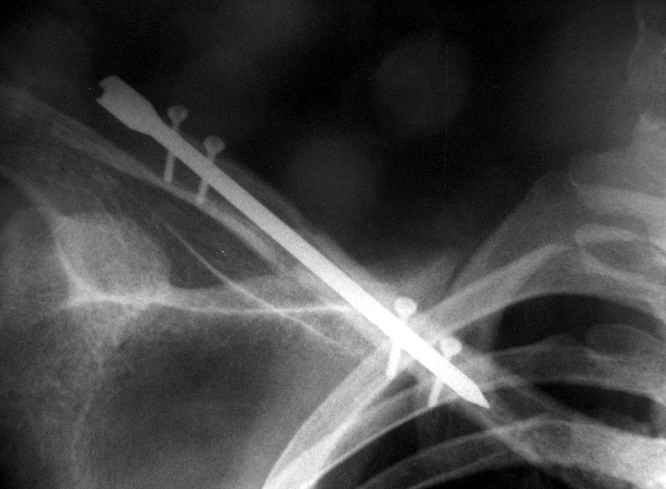

Виктор, если я не ошибаюсь, мы по Новосибу знакомы. Закрыто делаю так: после укладки на валик под лопатки со свешивающимся со стола локтем (руку можно под поясницу, а лучше на веревочку и кисть на живот. Порпобовать как отломки репонируются руками (обычно плохо), потом каждый отломок аккуратно цапкой захватываю и еще раз пробую репонировать. Это помогает выявить направление в котором репозиция дистигается легче всего и исключить наличие "мышечного перемота". Центральный отломок цапкой поднимаю и под кожей определяю его торец. Спицу в канал и рукой до упора, делее дрелью до выхода из кожи, потом дрель на другую сторону и спицу поглужаю под обрез отломка. Репозиция цапками за оба отломка. Пальцами определяется сопоставление, а ассистент пробивает спицу по каналу в переферический. После пробивания 2 - 3 см. уже теряется подвижность и это является контролем точности проведения. Далее как пожелаете. Понятно, что мы фиксируем наружной конструкцикй из 2 - 3 консольных спиц поперек в каждфй отломок, фиксированных на обычном резьбовом стержне на толстых шайбах.Доп.иммобилизация не нужна.

Мужик кочегар, срок нетрудоспособности 7 недель. Наружную конструкцию сняли через 3 недели. Далее без иммобилизации. Погруженную спицу можно убрать и через несколько месяцев, если жить не мешает.

Раньше не погружали, на рентгенограммах и натуре видно (последние 2 вложения). Как вариант спицы в периферическом отломке могут крепится на трехдырочную приставку, что дает возможность компрессии.

Укладка как при переломе, репозиция руками, а когда задавить не удается - однозубым крючком. Практически не открываемся (исключения составляют переломы с линией излома снаружи-внутрь сверху-вниз и острым концом - отломок маленький, а острый конец в мягких тканях путается, не сопоставить) Через акромион в клюциу 2 спицы гоним. две консольные в акромион, еще две в ключицу. Все спицы на стержень. Обычно держиться. Так и вывихи делаем, но там не все выходит, говорил уже.